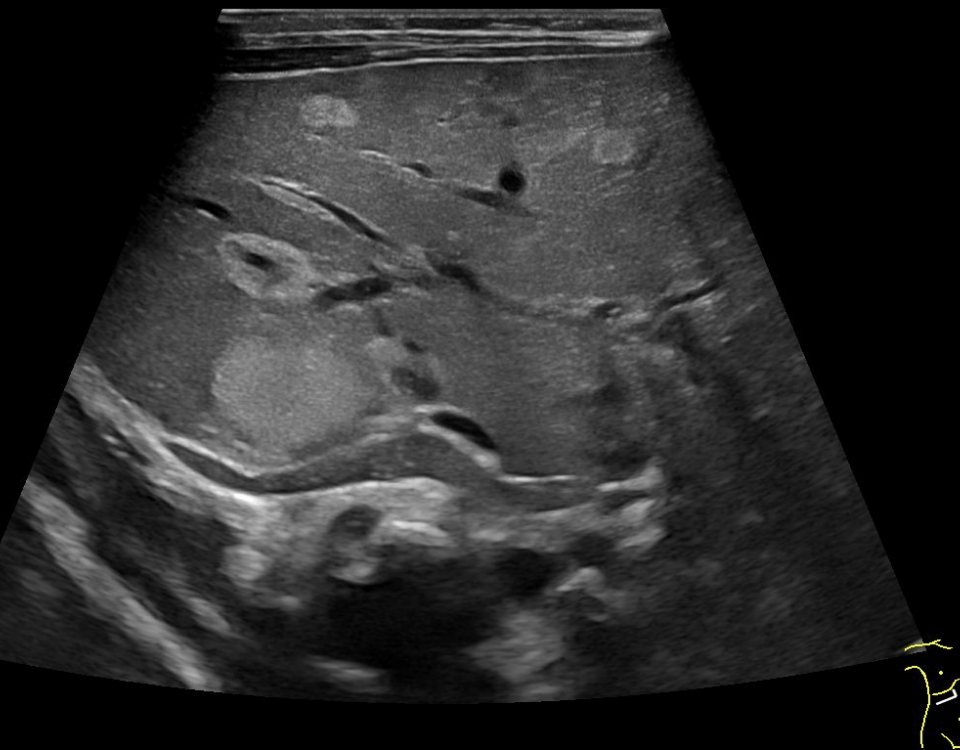

We present the case of a 59-year-old male, previously fit and well who presented to the General Practitioner with a 3 week history of epigastric pain, shortness of breath and unintentional weight loss. On examination, there was evidence of abdominal distension and palpable swelling of left testes. Initial investigation with US of the scrotum revealed dilated (maximally 5.3mm) left pampiniform plexus with retrograde flow on Doppler ultrasound and Valsalva manoeuvre, consistent with an extensive unilateral varicocele (Fig. 1 and 2). Subsequent abdominal ultrasound demonstrated moderate ascites, dilated common bile duct, large right sided pleural effusion and a large 14x14cm solid, vascular epigastric mass. This prompted urgent surgical referral and further cross-sectional imaging (Fig. 3). CT abdomen showed a large soft tissue density retro-peritoneal mass obliterating the portal mesenteric vein circulation and causing the left varicosity (Fig. 4). Ultrasound guided biopsy of the central abdominal mass confirmed a Stage IV Mantle cell Lymphoma.

Figure 3:A, B: Abdominal ultrasound images revealing the presence of a heterogeneous epigastric mass demonstrating internal vascularity on Colour Doppler imaging.